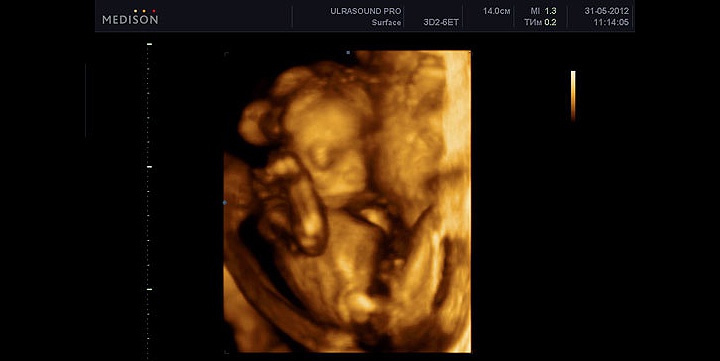

УЗИ

На 18 неделе при УЗИ видно половые органы малыша, и родители могут узнать пол. УЗИ показывает, как малыш двигается, сосет пальчики и толкается. Активно работает мимическая мускулатура, кроха тренирует рефлексы.

При УЗИ определяется вес плода по размерам.

Размеры

- Бипариентальный размер: 37–47 мм.

- Лобно-затылочный размер: 131–161 мм.

- Окружность головки: 131–161 мм.

- Окружность живота: 104–144 мм.

- Плечевая кость: 15–21 мм.

- Кости предплечья: 17–23 мм.

- Бедренная кость: 23–31 мм.

- Кости голени: 23–31 мм.

Плацента имеет толщину 2–2,5 см, степень зрелости равна нулю. Индекс околоплодных вод в норме 80–220 мм. УЗИ также позволяет оценить кровоток в плаценте и пуповине.

Возможные патологии на УЗИ

Исследование помогает выявить угрозу выкидыша, нарушения развития ребенка и патологию плаценты. При выявлении нарушений маму направляют к специалистам, а при необходимости — госпитализируют для сохранения беременности.